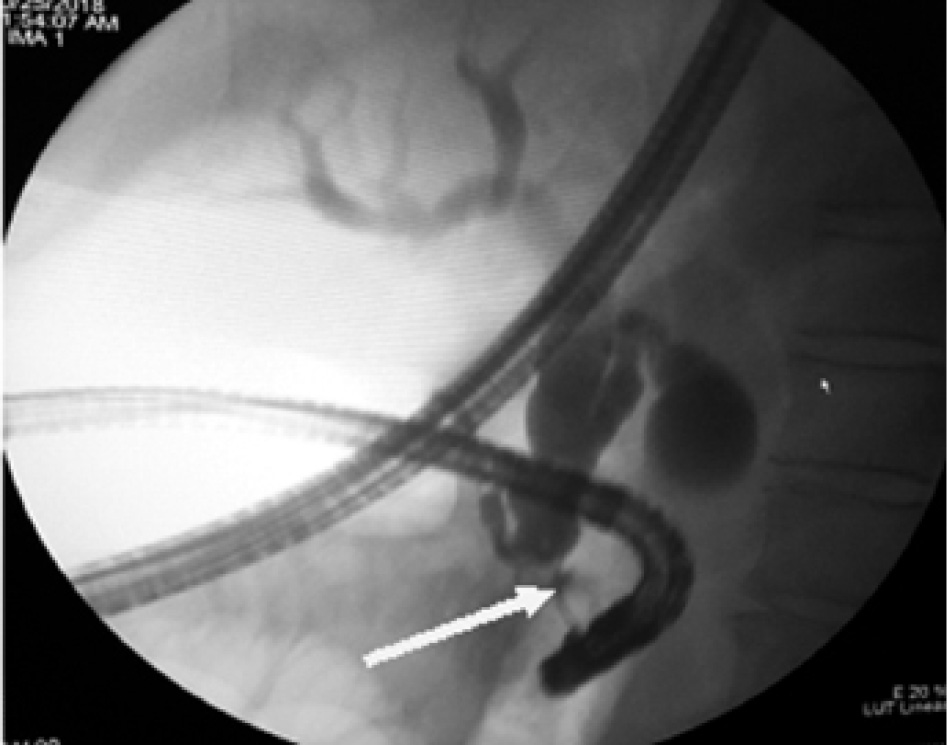

Наличие временного каркасного дренажа позволило подтвердить несостоятельность ПЕА рентгеноконтрастной фистулографией (рис. 6).

Рис. 6. Панкреатическая фистулография. Стрелками обозначены панкреатический проток и зона несостоятельности анастомоза